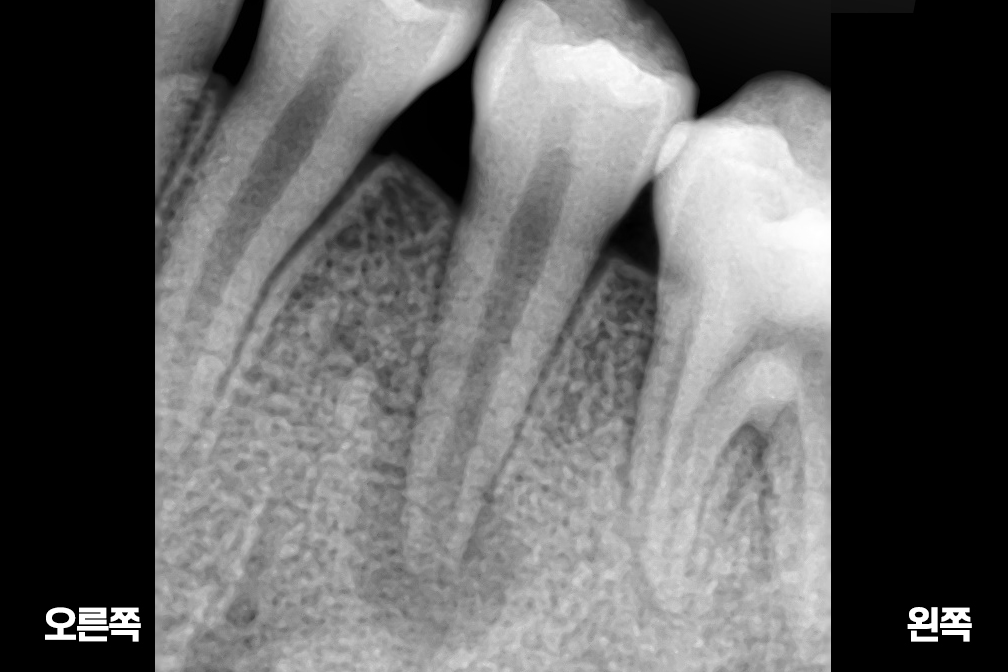

근관치료

After 2025년 6월 25일